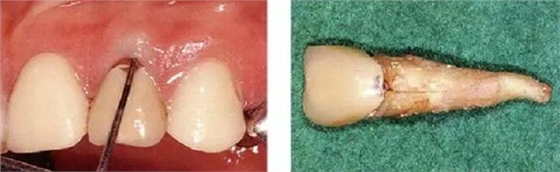

●外傷引起的附著喪失②

右上2修復(fù)物脫落而來院的患者(上圖是修復(fù)物臨時(shí)裝戴的照片)。頰側(cè)僅有一點(diǎn)有6mm的牙周袋。5個(gè)月前不存在此牙周袋。診斷為無法保存而進(jìn)行了拔牙。拔牙后,肉眼可清晰觀察到破折線。根據(jù)診查推斷為該深度牙周袋是由于牙根破折導(dǎo)致附著喪失,細(xì)菌沿著破折線進(jìn)入后破壞了牙周膜造成的。